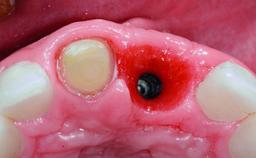

A 49-year-old female patient was referred for implant therapy to replace the upper right central incisor (tooth 11). The tooth had been assessed by an endodontist who diagnosed a vertical fracture of the root. The tooth had a hopeless prognosis and needed to be extracted. The patient was healthy and was not taking any medications. She was allergic to penicillin. The patient had high esthetic demands but her expectations were realistic. The extraoral examination revealed no facial asymmetries. The right temporomandibular joint demonstrated an opening click but was otherwise asymptomatic. The lip line was high with a significant gingival display.